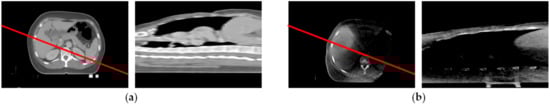

A cross-section of the CT image sequence could be drawn by taking a straight line crossing the tissue, extracting the pixels along this line on all the images, and arranging those pixels column by column tightly, making sure the order of the pixel column is consistent with the image in the sequence so it is an example of the cross-section of a CT sequence that could be used for registration. This simple cross-section already has two of three properties mentioned above: the encoding method is simple and robust, and the order of the pixel column is unaltered; it is very easy to inverse map to the order number of the image in the sequence. Additionally, this cross-section is also one of the CT slices in (x, z) projection plane (a more detailed elaboration is in Section 4 of this paper). Of course, this could reflect the change in the structure in the z direction. However, before using this cross-section, two sequences should be aligned in the (x, y) projection plane. As Figure 7 shows, without alignment, the same straight line may cut through different parts of tissue, and it could lead to the two cross-sections representing a different feature.

Figure 7.

The section of two sequences cut off by the same straight line, (a) the diagram of CT section line, and the cross-section rebuilt by the section line; (b) the cross-section of CBCT cut off by the same section line.